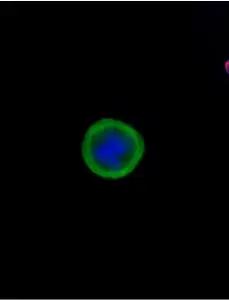

Example images from patient blood samples

Single mesenchymal CTCs - breast